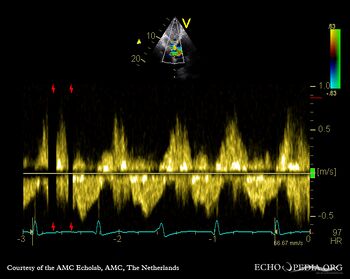

Pulsed-wave Doppler signal of hepatic veins: systolic flow reversal